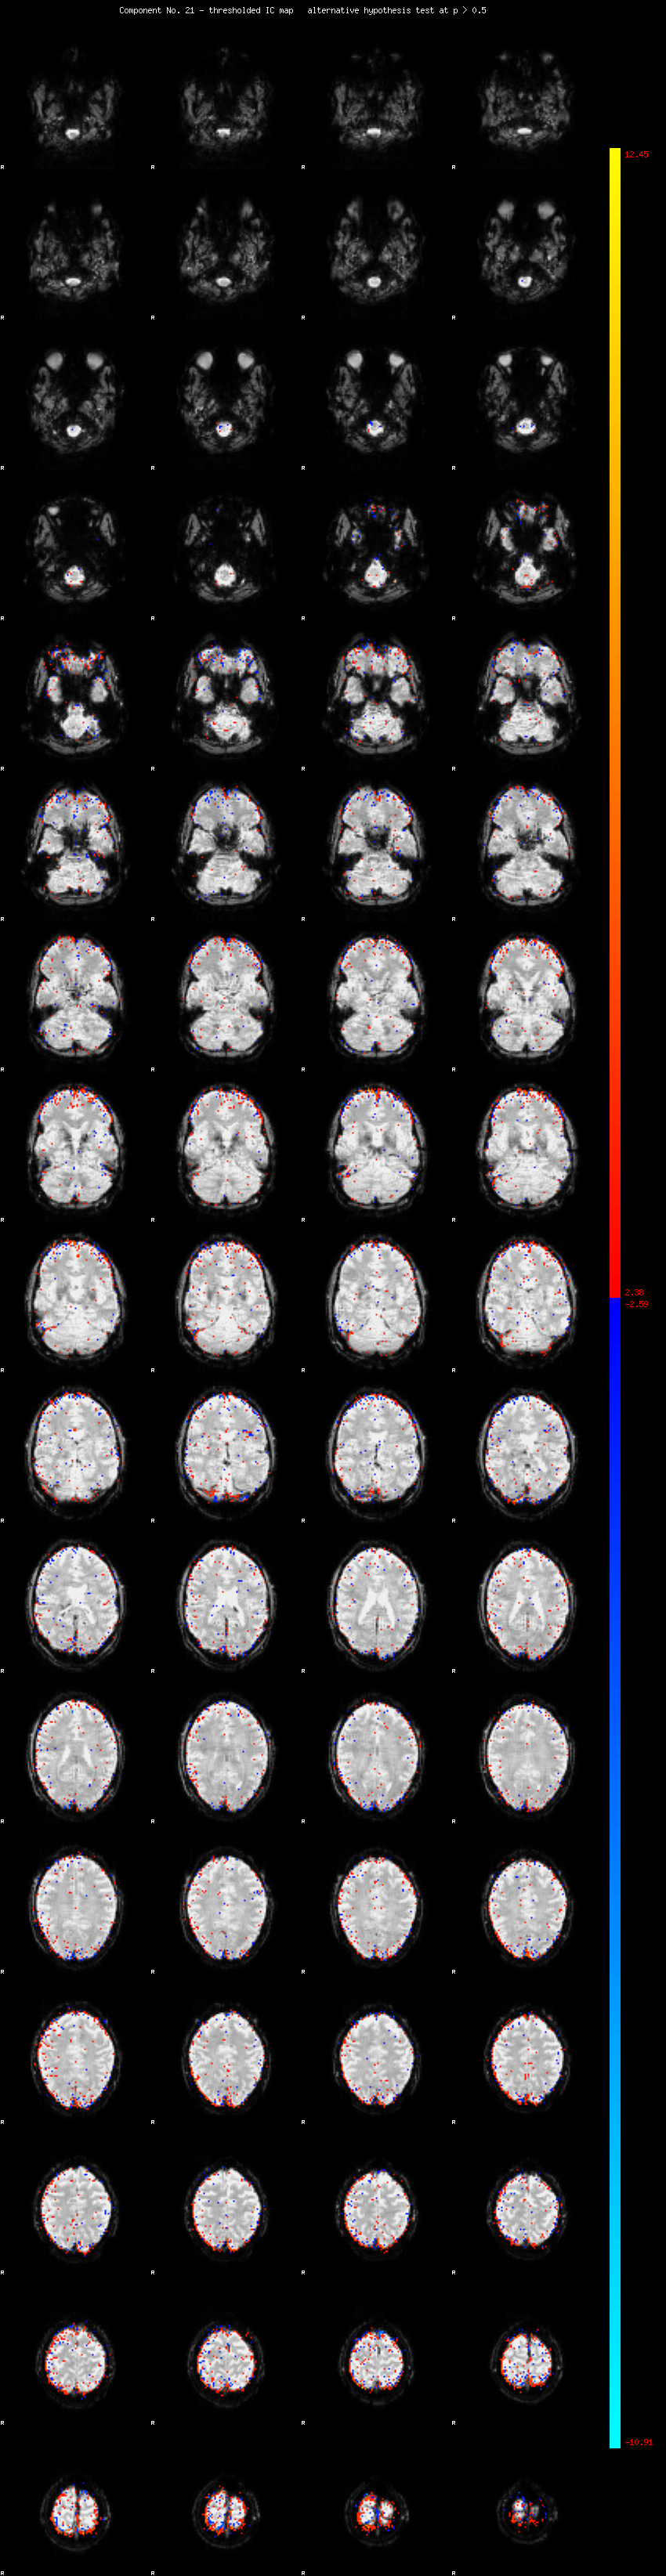

MELODIC Component 21

1.37 % of explained variance;     0.91 % of total variance

MMfit